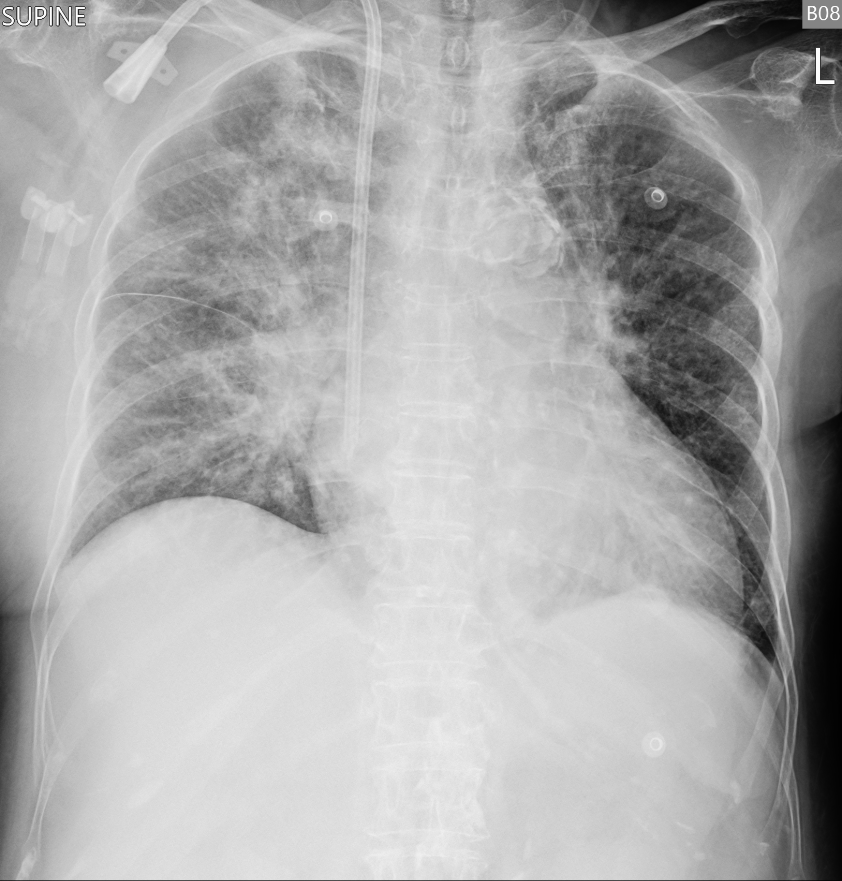

An 86-year-old woman with ESRD on HD, recurrent heart failure, prior PEA arrest, AF (CHA©üDS©ü-VASc 7), DM, HTN, dyslipidemia, and prior NSTEMI presented with sudden dyspnea, orthopnea, diarrhea, and desaturation at home. She appeared acutely ill on arrival, tachypneic with RR 30/min, BP 156/67 mmHg, pulse 78/min, GCS 15, and without peripheral edema. CXR showed increased opacities over both lung fields.

Relevant Test Results Prior to Catheterization